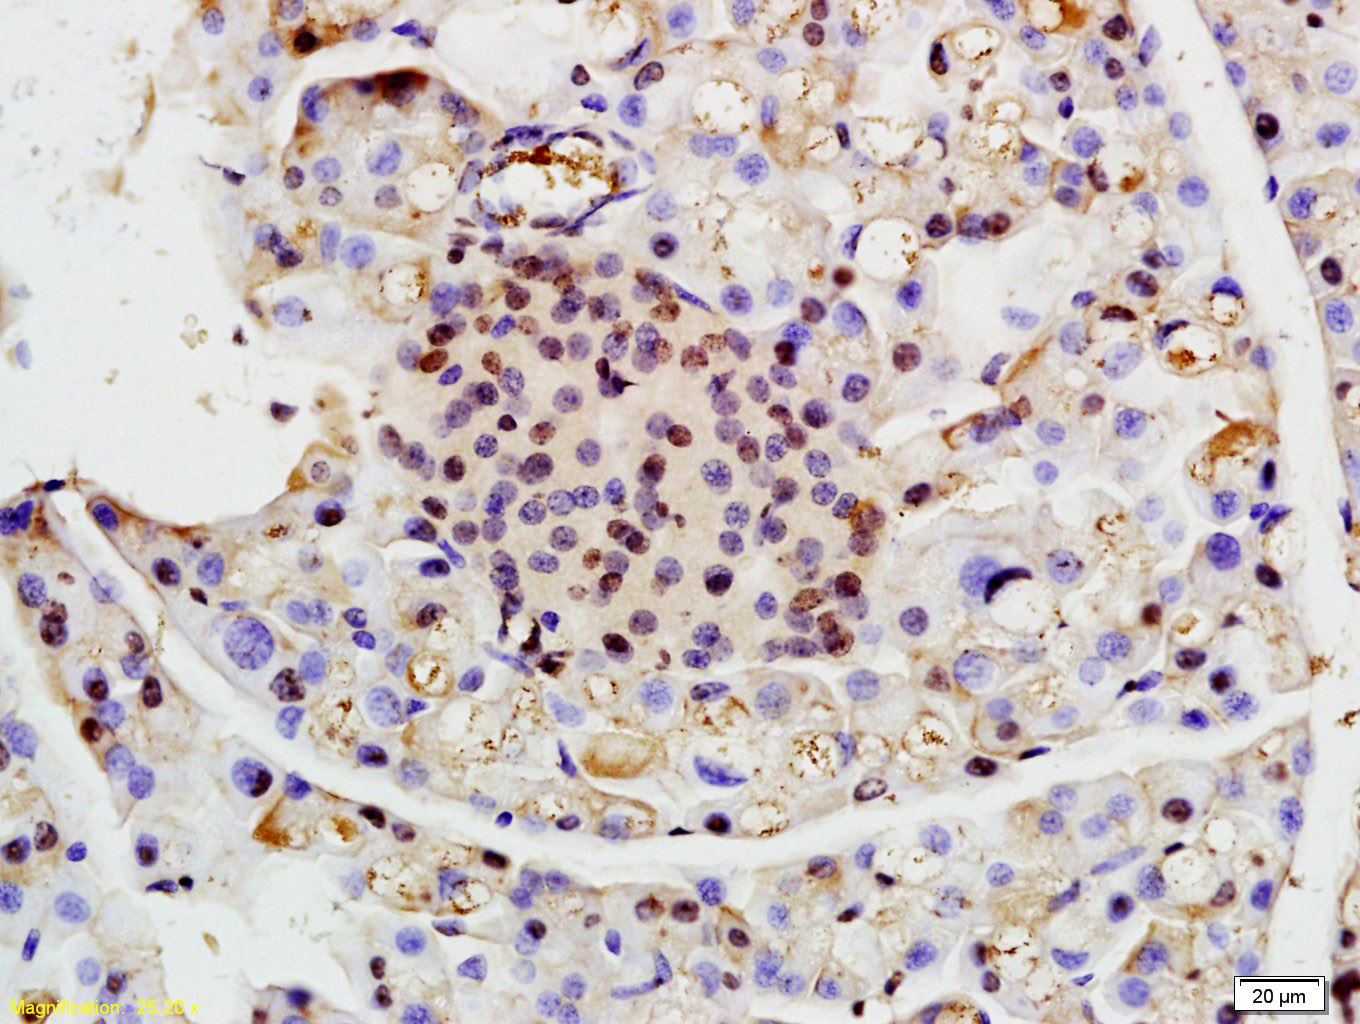

Tissue/cell: rat pancreas tissue; 4% Paraformaldehyde-fixed and paraffin-embedded; Antigen retrieval: citrate buffer ( 0.01M, pH 6.0 ), Boiling bathing for 15min; Block endogenous peroxidase by 3% Hydrogen peroxide for 30min; Blocking buffer (normal goat serum,C-0005) at 37∩ for 20 min; Incubation: Anti-RNF13 Polyclonal Antibody, Unconjugated(bs-9158R) 1:200, overnight at 4∑C, followed by conjugation to the secondary antibody(SP-0023) and DAB(C-0010) staining